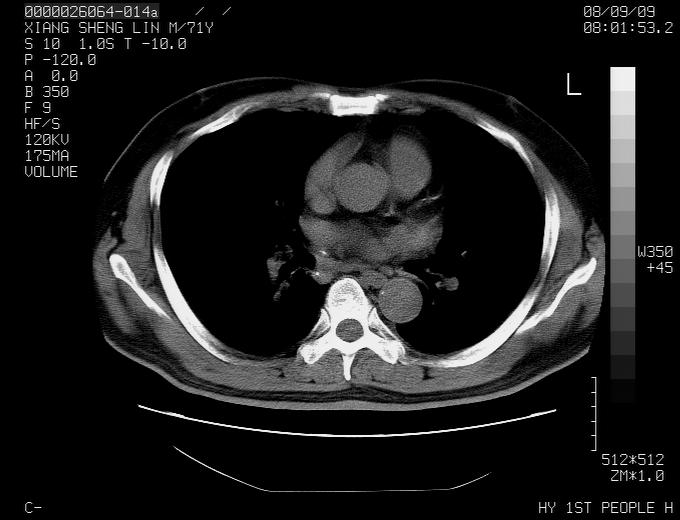

标题: CT15869:男性,71岁,因咳嗽而就诊,请讨论右上肺病变性质 [打印本页]

标题: CT15869:男性,71岁,因咳嗽而就诊,请讨论右上肺病变性质

患者,男性,71岁,因咳嗽而就诊,

典型的右肺中心性肺癌并纵隔淋巴结转移

右肺中心性肺癌并纵隔淋巴结转移可能性大!

考虑右肺中心性肺癌并右肺门及纵隔淋巴结转移。

1,右肺中心型ca,气管隆突旁淋巴结转移。